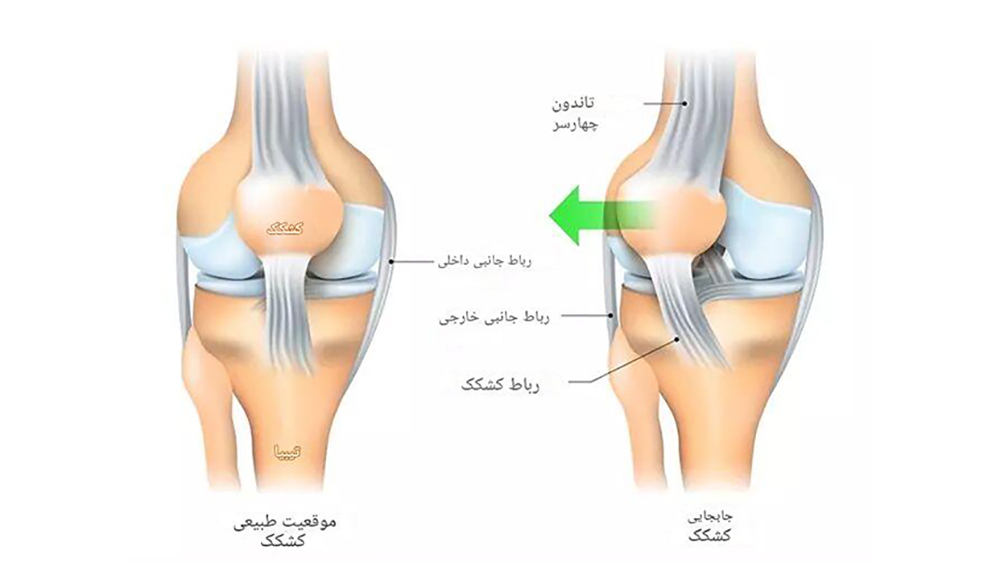

5. ناپایداری یا جابهجایی کشکک زانو

حرکت غیرطبیعی کشکک زانو (Patellar Instability) یکی دیگر از عوامل مهم است. این مشکل معمولاً به علت:

- ضربه مستقیم

- تصادفات

- آسیبهای ورزشی

- ضعف عضلات ران

- ایجاد میشود و عملکرد مفصل پاتلوفمورال را مختل میکند.

- اصلاح مشکلات کشکک زانو

زمانی که آسیبهای ساختاری شدید مانند پارگی رباطها، بیثباتی قابلتوجه مفصل پیشرفته وجود داشته باشد، درمان جراحی بهترین گزینه محسوب میشود. جراحی ممکن است بهصورت آرتروسکوپی (کمتهاجمی) یا جراحی باز انجام شود تا ساختارهای آسیبدیده ترمیم یا بازسازی شوند. بازسازی رباط صلیبی به بازگرداندن ثبات زانو کمک کرده و اصلاح مشکلات کشکک باعث بهبود حرکت طبیعی مفصل میشود. در موارد پیشرفته که مفصل بهشدت تخریب شده است، تعویض مفصل زانو میتواند درد را کاهش داده و توانایی حرکت بیمار را بهطور قابلتوجهی بازیابی کند.